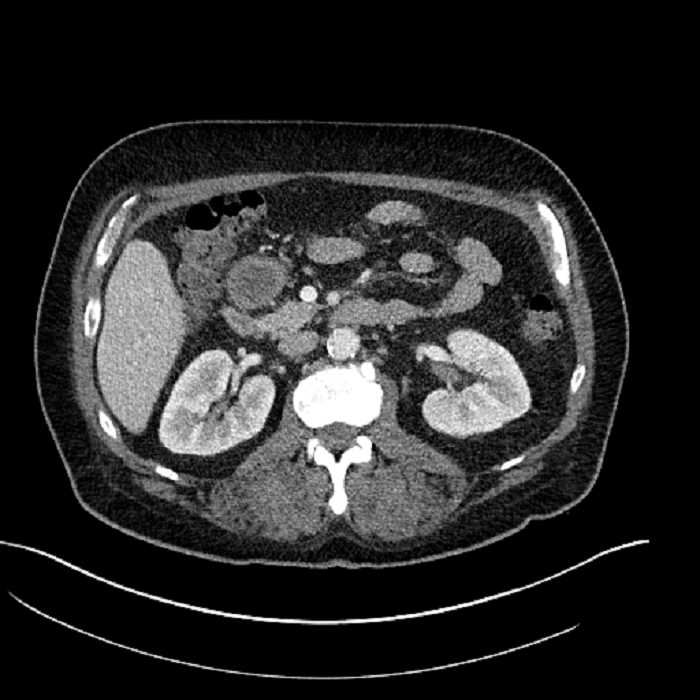

• Large fluid density structure in hepatic segments 7 and 8 measuring 10 x 7 x 7 cm with internal septation and circumferential ill-defined low density compatible with edema

• Clearly marginated fluid density structure in segment 7 and several other scattered tiny hypodensities, which likely represent cysts

Acute sigmoid diverticulitis complicated by a small contained perforation and a large abscess in the right hepatic lobe. Additional small subcapsular abscesses along the anterior margin of the left hepatic lobe.

• The classic CT imaging appearance is a double target sign with internal low density surrounded by an internal enhancing rim (capsule) and a low density external rim (edema)

Hepatic abscess showing the double target sign with low density internally surrounded by a thin inner enhancing rim (red arrow) and ill-defined outer low density rim (yellow arrow). Blue arrow indicates an internal septation. Red arrows: additional smaller subcapsular abscesses. Red arrow: focal contained perforation associated with diverticulitis.